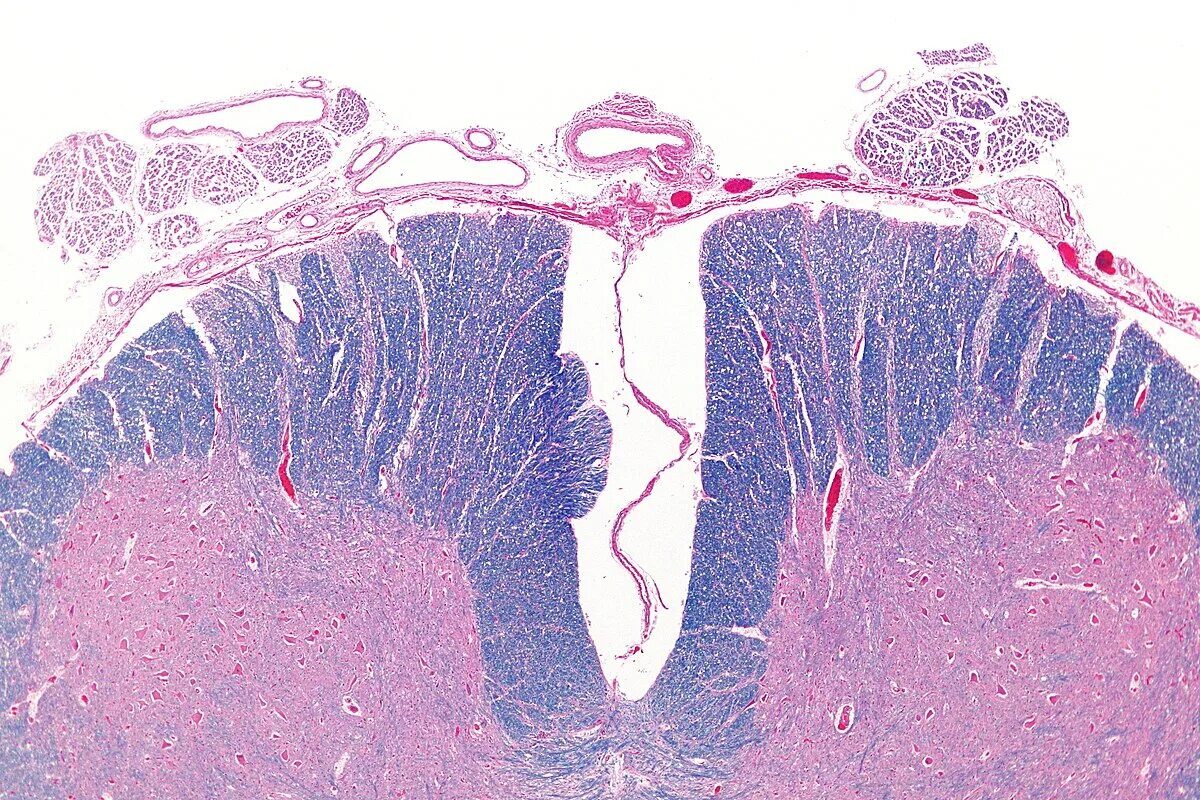

Гистологические варианты